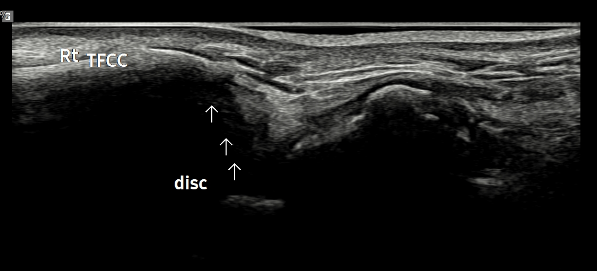

- 치료기간 : 25 . 6 . 9 ~ 25 . 10 .27

- 치료횟수 : 4 사이클(20) 회

치료전

치료 후

힘줄 두께 감소 및 전체적인 파열 부위 축소 & 골극 감소

-> 검사상 파열은 여전히 있지만 운동 이후에도 통증이 크게 없어서 치료 종료 후 3~4주정도 텀 두고 관찰 예정